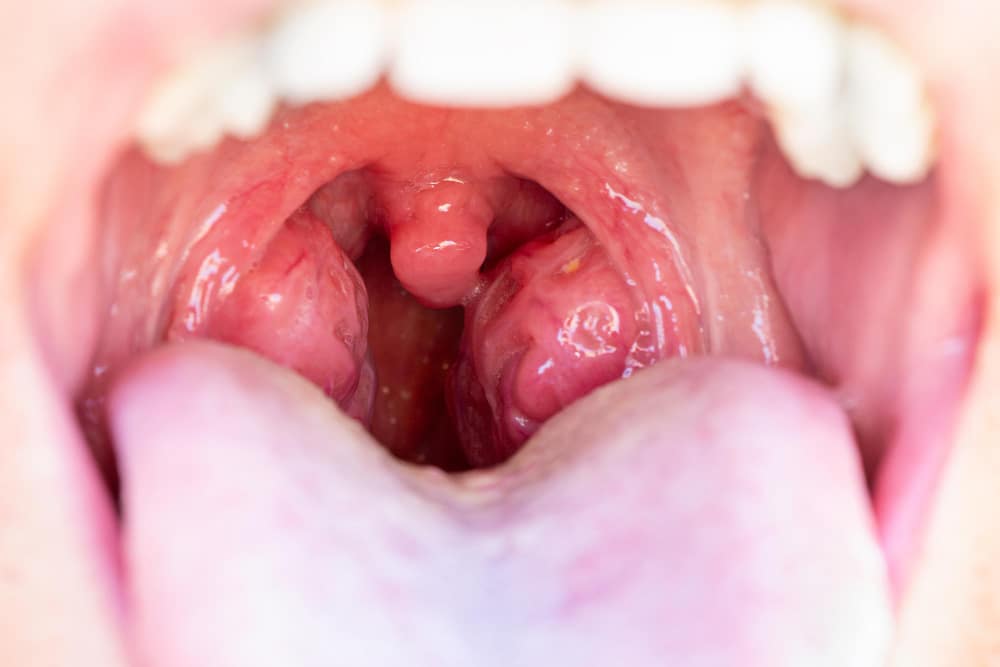

Tonsillitis and Strep Throat: How to Tell the Difference and Find Relief

Tonsillitis and strep throat are common causes of a sore throat. Both can make swallowing painful and cause discomfort. However, there are important differences between tonsillitis and strep throat. Knowing these differences helps you find the right relief for a sore throat. In this blog, we will explain the symptoms of tonsillitis, the signs of […]